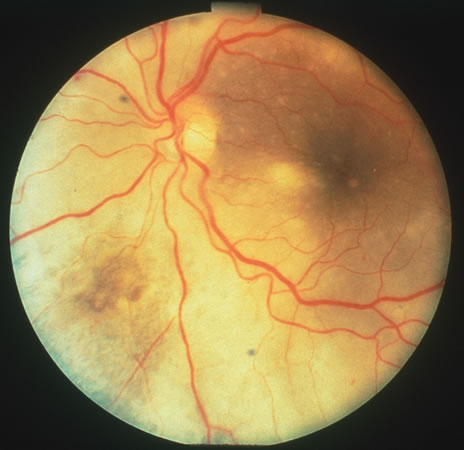

In primary ocular HSV infections, a severe follicular conjunctivitis with regional adenopathy is present. Vesicles may appear on the eyelid skin or lid margin, producing blepharitis (Fig. 3). Corneal involvement initially takes the form of a superficial punctate keratitis, which may progress to dendritic or geographic ulceration. Stromal infiltrates and uveitis are less common and relatively mild in primary disease. In uncomplicated cases, lesions usually heal completely in 2 to 3 weeks without scarring. Most cases of ocular HSV are recurrences. Recrudescent ocular herpes may take the form of dendritic or geographic ulcers, recurrent erosions, interstitial or disciform stromal keratitis, and anterior uveitis.3 HSV may also be an agent of retinitis and acute retinal necrosis (Fig. 4).